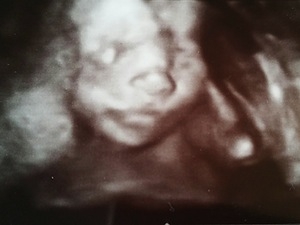

Wunder der Technik - Wunder des Lebens - Tagebücher aus der Schwangerschaft von Kristin aus Jena

Eine neue wunderbare, aufregende und vielleicht auch lang erwartete Lebenszeit beginnt. Für unsere Tagebücher-Blogs haben wir immer 3-4 schwangere Frauen in unterschiedlicher Schwangerschaftsphase, die in freudiger Erwartung über jede Woche dieser spannenden Zeit schreiben, uns und die vielen tausend Follower:innen daran teilhaben lassen und damit unvergessliche Momente schaffen.